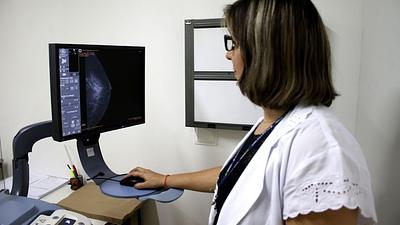

IA antecipa risco de câncer de mama por até cinco anos

Modelo de inteligência artificial analisa mamografias para avaliar risco do desenvolvimento da doença. Técnica pode ajudar a identificar casos não detectados pelo exame tradicional.